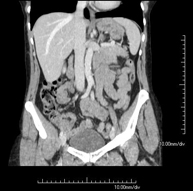

- Angio-TC aorta abdominal  Prueba diagnóstica no invasiva que consiste en el estudio de la arteria aorta abdominal obteniendo imágenes de alta definición anatómica mediante el empleo de un equipo de TC (Tomografía Computarizada) y de contraste yodado. La calidad de las imágenes permite realizar reconstrucciones en 2D y 3D gracias a estaciones de trabajo especializadas en el estudio arterial. Está indicado en aquellos pacientes con enfermedad vascular (aterosclerosis), en aneurismas de aorta, en pacientes con dolor abdominal de posible origen vascular, en estudios pre-quirúrgicos de lesiones adyacentes a la aorta abdominal como "mapa" vascular, etc. La información obtenida de forma no invasiva es indispensable para los pacientes que requieren tratamiento percutáneo o quirúrgico. En aquellos pacientes que solo requieren un seguimiento de las lesiones vasculares, esta técnica es la técnica no invasiva de elección junto con la angio-RM. Prueba diagnóstica no invasiva que consiste en el estudio de la arteria aorta abdominal obteniendo imágenes de alta definición anatómica mediante el empleo de un equipo de TC (Tomografía Computarizada) y de contraste yodado. La calidad de las imágenes permite realizar reconstrucciones en 2D y 3D gracias a estaciones de trabajo especializadas en el estudio arterial. Está indicado en aquellos pacientes con enfermedad vascular (aterosclerosis), en aneurismas de aorta, en pacientes con dolor abdominal de posible origen vascular, en estudios pre-quirúrgicos de lesiones adyacentes a la aorta abdominal como "mapa" vascular, etc. La información obtenida de forma no invasiva es indispensable para los pacientes que requieren tratamiento percutáneo o quirúrgico. En aquellos pacientes que solo requieren un seguimiento de las lesiones vasculares, esta técnica es la técnica no invasiva de elección junto con la angio-RM.

- Angio-TC aorto-ilíaco Prueba diagnóstica no invasiva que consiste en el estudio de las arterias ilíacas y la aorta abdominal obteniendo imágenes de alta definición anatómica mediante el empleo de un equipo de TC (Tomografía Computarizada) y de contraste yodado. La calidad de las imágenes permite realizar reconstrucciones en 2D y 3D gracias a estaciones de trabajo especializadas en el estudio arterial. Esta prueba está especialmente indicada como estudio pre-quirúrgico (mapa vascular) antes de intervenciones percutáneas o quirúrgicas de aorta abdominal, como el estudio complementario en pacientes con isquemia de miembros inferiores, etc. Prueba diagnóstica no invasiva que consiste en el estudio de las arterias ilíacas y la aorta abdominal obteniendo imágenes de alta definición anatómica mediante el empleo de un equipo de TC (Tomografía Computarizada) y de contraste yodado. La calidad de las imágenes permite realizar reconstrucciones en 2D y 3D gracias a estaciones de trabajo especializadas en el estudio arterial. Esta prueba está especialmente indicada como estudio pre-quirúrgico (mapa vascular) antes de intervenciones percutáneas o quirúrgicas de aorta abdominal, como el estudio complementario en pacientes con isquemia de miembros inferiores, etc.

- Angio TC d'aorta abdominal Prova diagnòstica no invasiva que consisteix en l'estudi de l'artèria aorta abdominal amb l'obtenció d'imatges d'alta definició anatòmica mitjançant l'ús d'un equip de TC (Tomografia Computaritzada) i contrast iodat. La qualitat de les imatges permet realitzar reconstruccions en 2D i 3D gràcies a estacions de treball especialitzades en l'estudi arterial. Està indicat en aquells pacients que pateixen malaltia vascular (arteriosclerosi), aneurismes d'aorta, en pacient amb dolor abdominal d'un possible origen vascular, en estudis prequirúrgics de lesions adjacents a l'aorta abdominal com el "mapa" vascular, etc. La informació obtinguda de forma no invasiva és indispensable per als pacients que requereixen tractament percutani o quirúrgic. En aquells pacients que només requereixen un seguiment de les lesions vasculars, aquesta tècnica és la tècnica no invasiva d'elecció juntament amb l'angio RM. Prova diagnòstica no invasiva que consisteix en l'estudi de l'artèria aorta abdominal amb l'obtenció d'imatges d'alta definició anatòmica mitjançant l'ús d'un equip de TC (Tomografia Computaritzada) i contrast iodat. La qualitat de les imatges permet realitzar reconstruccions en 2D i 3D gràcies a estacions de treball especialitzades en l'estudi arterial. Està indicat en aquells pacients que pateixen malaltia vascular (arteriosclerosi), aneurismes d'aorta, en pacient amb dolor abdominal d'un possible origen vascular, en estudis prequirúrgics de lesions adjacents a l'aorta abdominal com el "mapa" vascular, etc. La informació obtinguda de forma no invasiva és indispensable per als pacients que requereixen tractament percutani o quirúrgic. En aquells pacients que només requereixen un seguiment de les lesions vasculars, aquesta tècnica és la tècnica no invasiva d'elecció juntament amb l'angio RM.

- Angio TC d'aorta-ilíaca Prova diagnòstica no invasiva que consisteix en l'estudi de les artèries ilíaques i l'aorta abdominal amb l'obtenció d'imatges d'alta definició anatòmica mitjançant l'ús d'un equip de TC (Tomografia Computaritzada) i contrast iodat. La qualitat de les imatges permet realitzar reconstruccions en 2D i 3D gràcies a estacions de treball especialitzades en l'estudi arterial. Aquesta prova està especialment indicada com a estudi prequirúrgic (mapa vascular) abans d'intervencions percutànies o quirúrgiques d'aorta abdominal, estudi complementari en pacients amb isquèmia de membres inferiors, etc. Prova diagnòstica no invasiva que consisteix en l'estudi de les artèries ilíaques i l'aorta abdominal amb l'obtenció d'imatges d'alta definició anatòmica mitjançant l'ús d'un equip de TC (Tomografia Computaritzada) i contrast iodat. La qualitat de les imatges permet realitzar reconstruccions en 2D i 3D gràcies a estacions de treball especialitzades en l'estudi arterial. Aquesta prova està especialment indicada com a estudi prequirúrgic (mapa vascular) abans d'intervencions percutànies o quirúrgiques d'aorta abdominal, estudi complementari en pacients amb isquèmia de membres inferiors, etc.